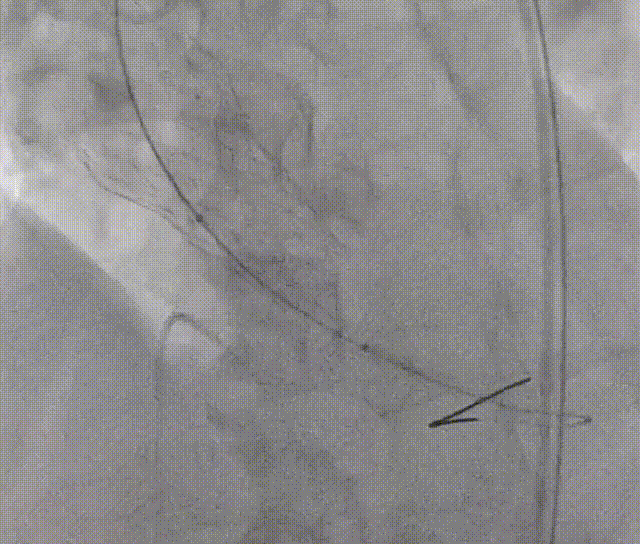

再次与根部造影对比

通过与术前主动脉根部造影的对比,确认两侧深度平均但较临界,可谨慎操作下尝试球囊后扩张以使流入端瓣架充分膨胀贴合自体瓣环,减少瓣周漏。

23mm Z-Med后扩张

在评判植入深度是否合理时,应特别关注瓣架形态,特别是瓣架底部扩张形态。如底部呈现“收口”形态,应谨慎评估植入深度,必要时回收瓣膜,调整为更深的释放位点;

当瓣膜完全释放后,瓣架仍呈“收口”形态,应充分评估后扩风险与获益,决定是否要后扩;

如需后扩,球囊充盈时建议轻推球囊,且待完全回抽球囊后再停起搏 ,以降低瓣膜脱位风险。